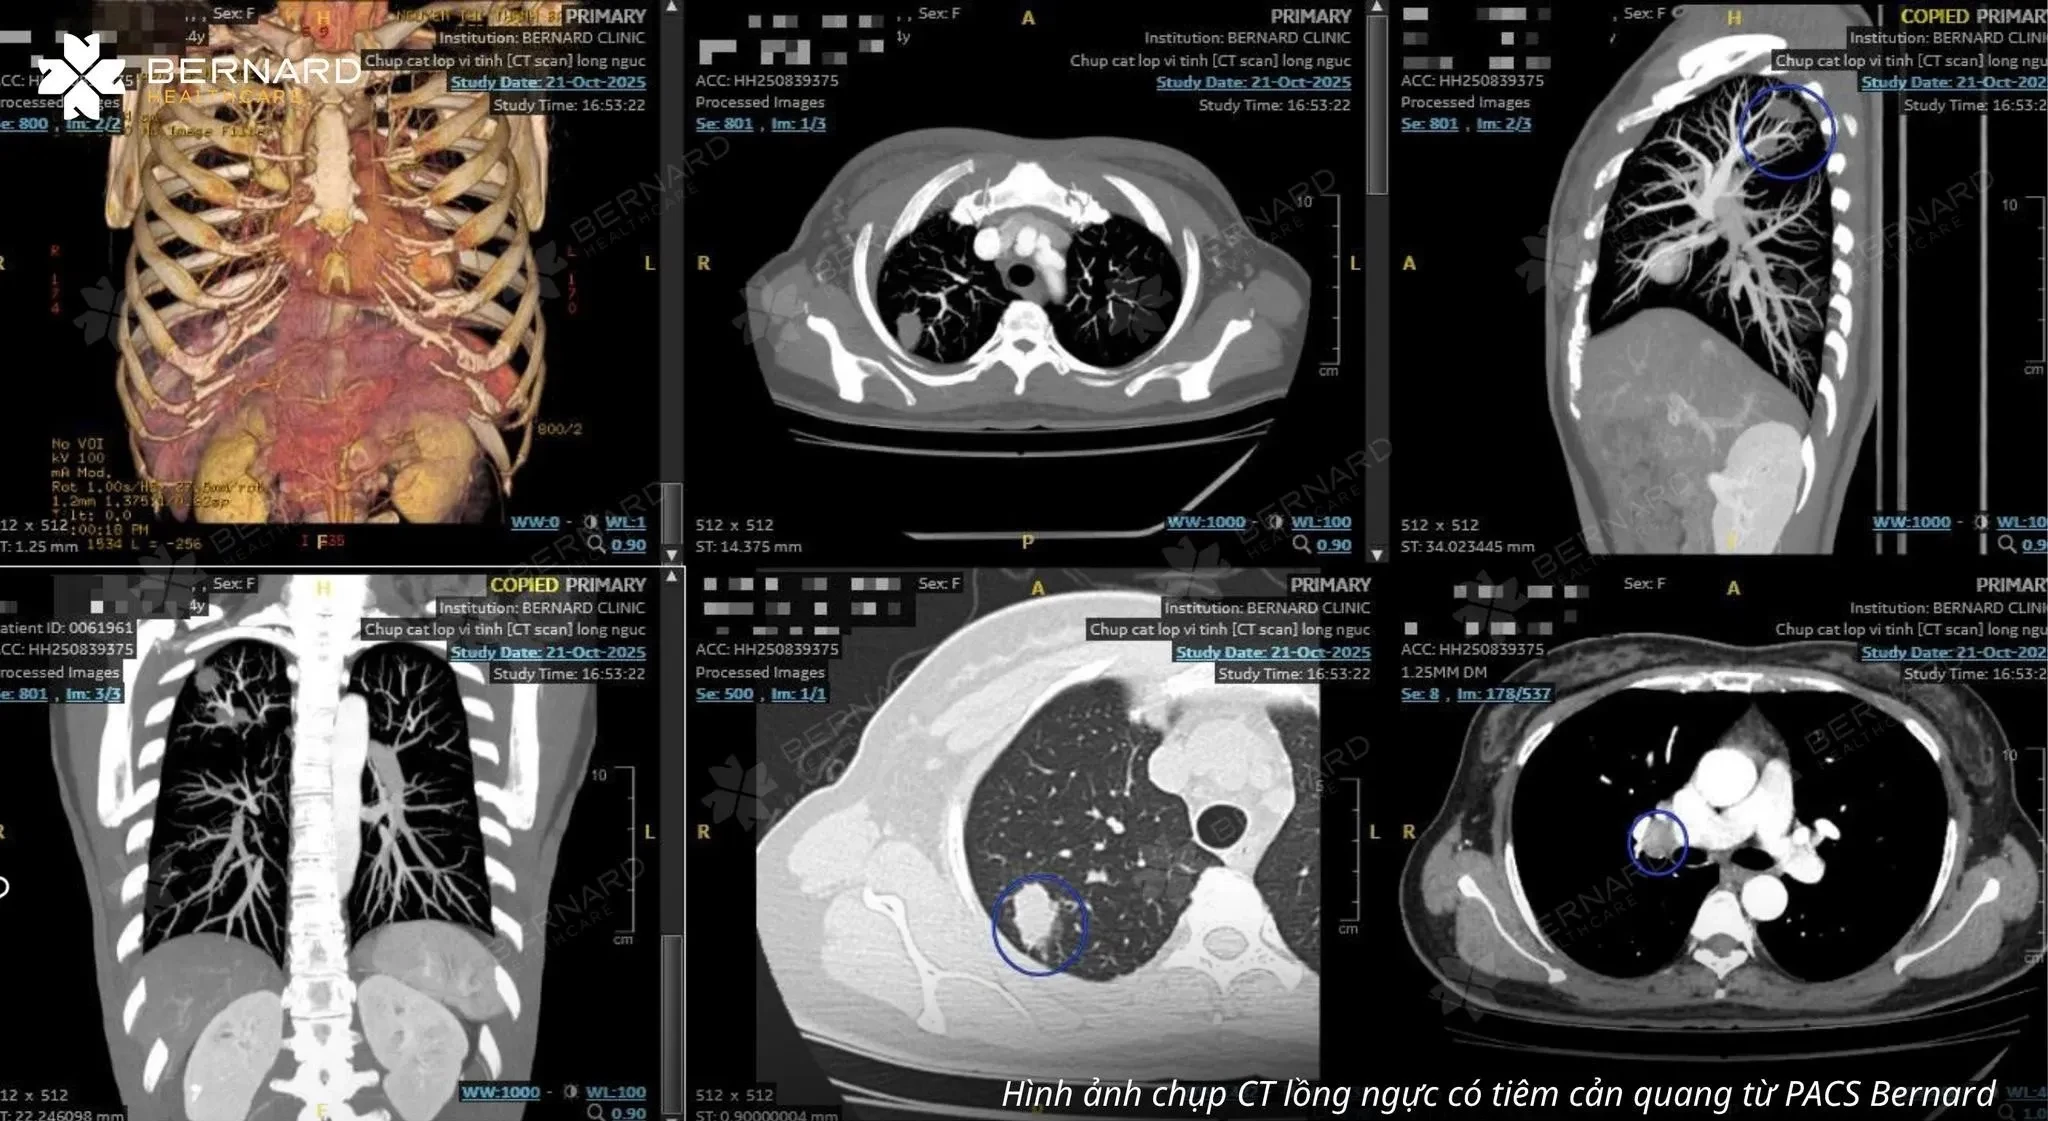

Đồng thời, với mục tiêu kiểm tra lại chi tiết bất thường ở cung động mạch chủ và tầm soát dự phòng các bệnh lý phổi nguy hiểm - đặc biệt ở nhóm nguy cơ cao như người trên 60 tuổi, bà K. đã thực hiện thêm chụp cắt lớp (CT Scan) phổi liều thấp.

Kết quả CT Scan phổi liều thấp cho thấy một tổn thương choán chỗ thùy dưới phổi trái (S10), kích thước khoảng 1.5 x 2.5cm, đậm độ mô, bờ tua gai, kèm co kéo mô phổi xung quanh. Những đặc điểm hình ảnh này gợi ý u phổi ác tính - cần kết hợp sinh thiết để xác định chính xác bản chất của tổn thương.

Đáng chú ý, kết quả CT Scan phổi còn đồng thời ghi nhận một số hạch trung thất nghi di căn với hạch lớn nhất thuộc nhóm 2, các nốt nhỏ quanh rãnh liên thùy bé phổi phải (đường kính khoảng 3mm) và nốt dưới màng phổi thùy lưỡi (đường kính khoảng 7mm). Đây có thể là dấu hiệu tổn thương đã bước vào giai đoạn di căn hạch trung thất. Tuy nhiên, chưa ghi nhận bằng chứng lan rộng ra các cơ quan xa.